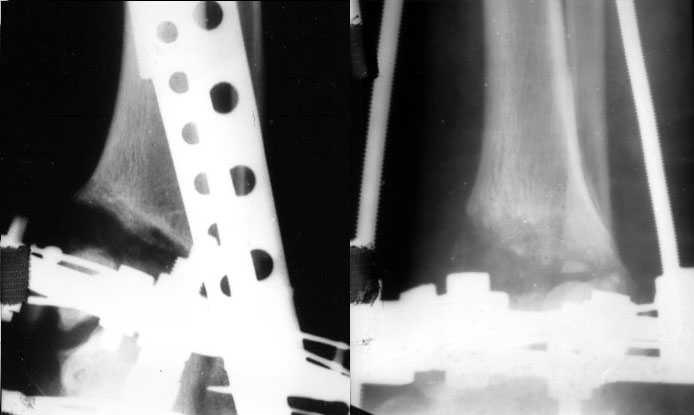

Померять однозначно сложно. Зато операция с аппаратом проще и быстрее. Провел-собрал-через прокол рубанул-1 шов-иди отдыхай. А открыто - и клиновидный дефект одномоментно может получиться большой, и очень короткий дистальный отломок фиксировать не очень будет удобно, потом на итоговых снимках вдруг обнаружится, что уголок не совсем такой, как планировали... Про другие возможные проблемы вспомнить можно...

Есть возможность аппаратом все исправить, а потом перейти на внутреннюю фиксацию.